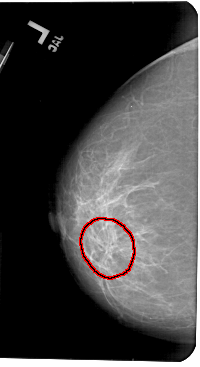

A_1436_1.LEFT_MLO

LEFT_MLO LINES 5491 PIXELS_PER_LINE 3046 BITS_PER_PIXEL 12 RESOLUTION 43.5 OVERLAY

FILE: A_1436_1.LEFT_MLO.OVERLAY

TOTAL_ABNORMALITIES 1

ABNORMALITY 1

LESION_TYPE MASS SHAPE ARCHITECTURAL_DISTORTION MARGINS ILL_DEFINED

ASSESSMENT 4

SUBTLETY 3

PATHOLOGY BENIGN

TOTAL_OUTLINES 1

BOUNDARY